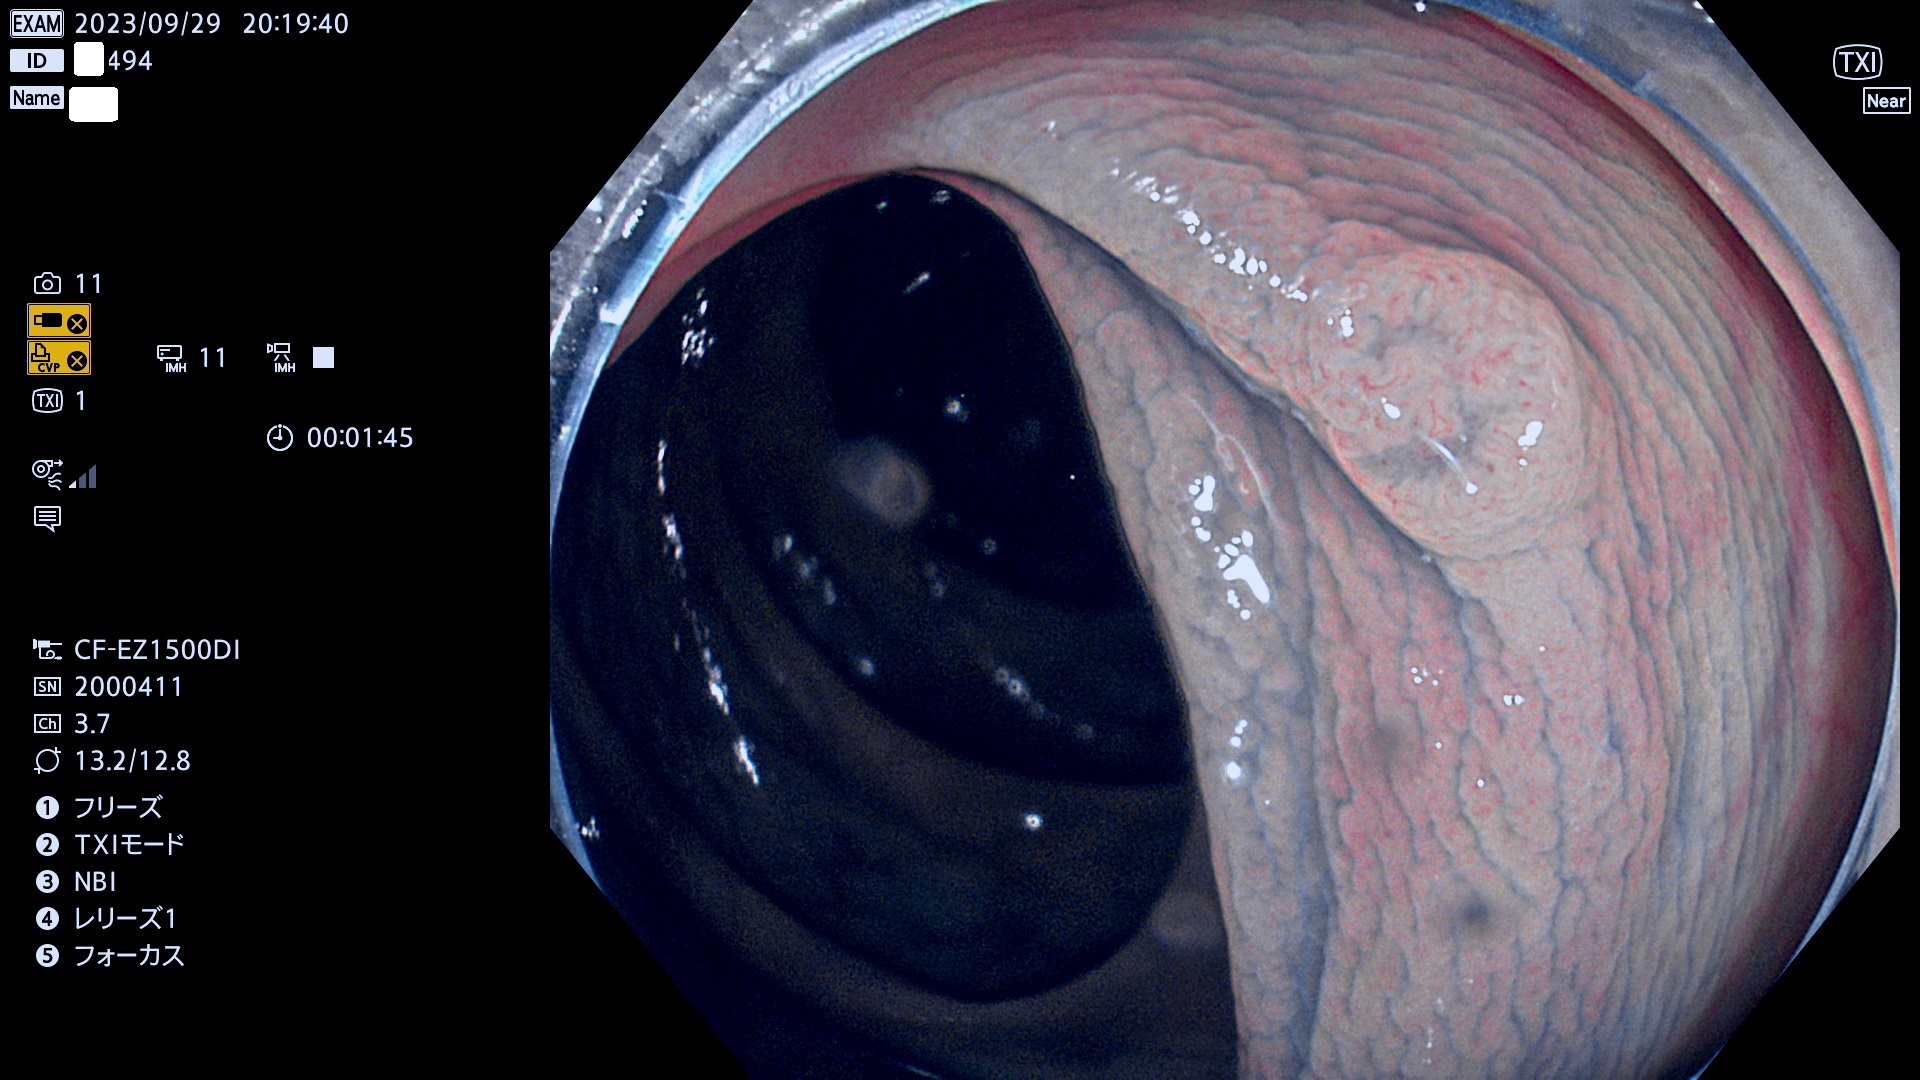

表面型腺腫(Flat Adenoma)の中で、完全に平坦な物をUb、陥凹している物をUcと呼びます。平坦隆起型(Ua)よりも、発見が難しく危険な病変です。このタイプは「内視鏡後・大腸癌の重要犯人」であり、この発見率は「腺腫発見率」よりも、重要な意味があります。

毎週の検査(木・金・土・日)に発見されたUb、Uc型・腺腫を、その週の日曜の夜にUPし1週間、提示します。

抽出の対象期間 2023年9月28日(木)〜10月1(日)の4日間(48件の検査)8件